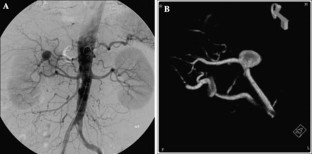

Fig. 2.